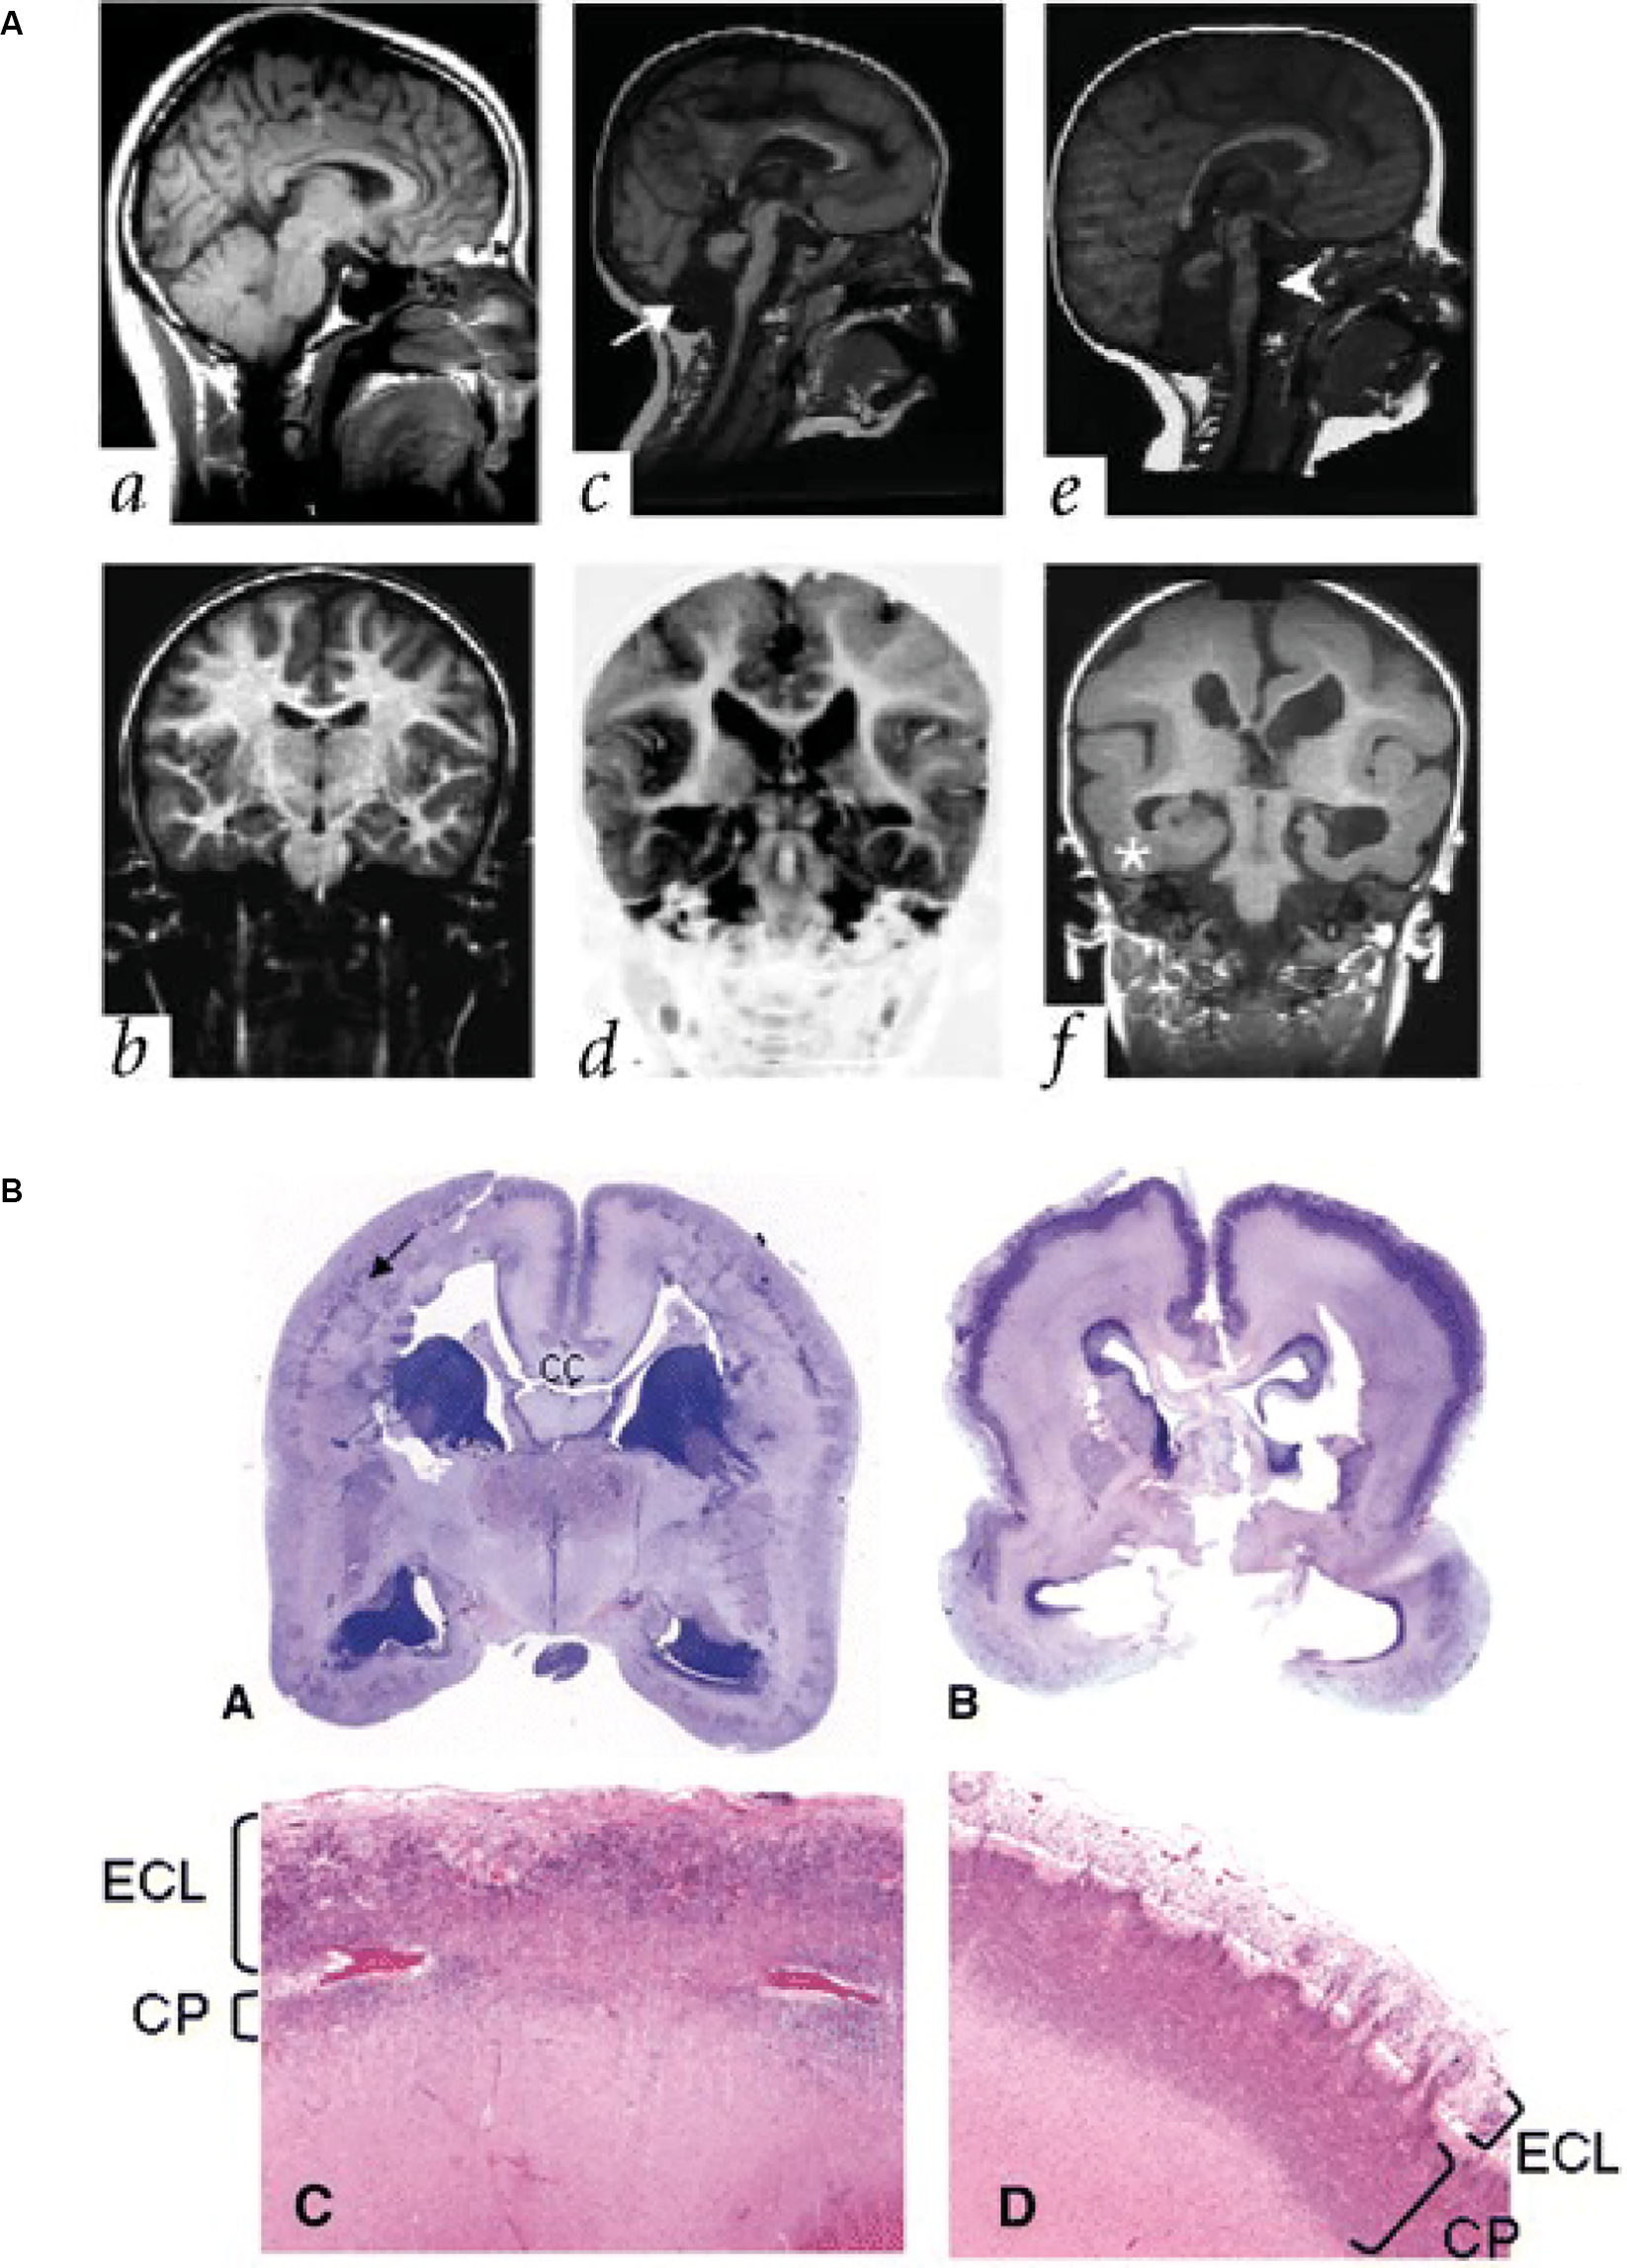

Reelin is an ECM glycoprotein (Hynes and Naba, 2012) secreted by several cell types, including the Cajal Retzius cells, early in the human fetal cortex (D’Arcangelo et al., 1995; Meyer et al., 2002). Mutations in the human gene RELN are linked to various neurodevelopmental disorders, including schizophrenia, bipolar disorder, and autism spectrum disorder (Ishii and Maeda, 2008; Lakatosova and Ostatnikova, 2012). RELN mutations are also known to cause type I lissencephaly, with abnormal lamination of the cortical plate and a loss of cortical folding (Figure 4A; Hong et al., 2000). The mechanisms underlying this malformation have been elucidated in mouse models (Hong et al., 2000; Fatemi, 2001; Rice and Curran, 2001; Pérez-Martínez et al., 2012; Sekine et al., 2012; Hirota and Nakajima, 2017; Mizukami et al., 2018), which show that Reelin is important for directing the migration of newborn neurons and the correct positioning of these neurons in the cortical plate.

Figure 4. Lissencephaly in patients with mutations in ECM and ECM-associated genes. (A) Parasagittal (upper panels) and coronal (lower panels) MRI from patients with a normally developing brain (a,b), and two patients with lissencephaly associated with RELN mutations (c,d; e,f). Note the thickened cortex and reduced folding present. Adapted from Hong et al. (2000). (B) Images showing examples of cobblestone lissencephaly in a 19 pcw fetus with a POMT1 mutation (A,C, left panels) and 26 pcw fetus with a POMGNT1 mutation (B,D, right panels). The top panels show whole-mount sections of the brain. Arrow indicates impoverished cortical plate in the top left panel. The lower panels show higher magnification images of the cortical plate from these fetuses. Note the reduced size of the cortical plate (CP) and the thickened extracortical layer (ECL) in the lower left panel, but the thin ECL in the lower right panel. CC indicates the corpus callosum. Adapted from Devisme et al. (2012).

The role of ECM in neuronal migration disorders is relatively common. Patients with another type of lissencephaly, cobblestone lissencephaly, also have mutations in genes that alter ECM function. In particular, the enzymes POMT1/2 that glycosylate the ECM receptor alpha-dystroglycan have been found in patients with cobblestone lissencephaly (Figure 4B; Devisme et al., 2012) and in Walker-Warburg syndrome (De Bernabé et al., 2002; Van Reeuwijk et al., 2005). Mutations in the genes that encode for the laminin subunits beta 2 and gamma 2 (LAMB2 and LAMC2) have also been associated with disorganisation of the cortical layers, similar to cobblestone lissencephaly (Radner et al., 2013), as have mutations in the laminin subunit beta 1 (LAMB1; Radmanesh et al., 2013). These mutations are thought to lead to these disorders via disruption of the pial basement membrane, which lies at the top of the cortical plate. This disruption enables migrating neurons to bypass their usual stop signals, migrating above the cortical plate and creating a bumpy, cobblestone-like appearance (Radner et al., 2013).